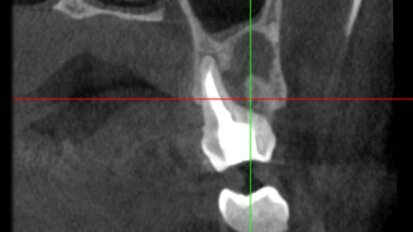

Atraumatic extraction of maxillary first premolar

A 70-year-old female patient visited our clinic owing to a fractured maxillary first molar. Tooth #24 had previously had a large composite restoration that ...